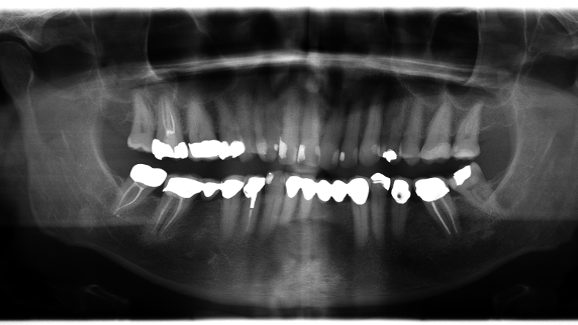

A 46-year-old male patient came to the clinic for a check-up. A native panoramic image (CRANEX D, dose area product DAP 70mGy/cm2) revealed a symptomless apical periodontitis in a root canal treated d17. Root canal treatment had been performed 4 years earlier (Fig. 1).